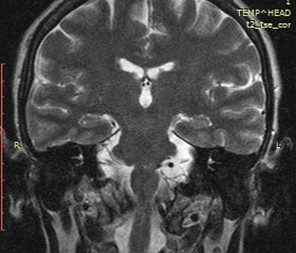

По данным МРТ головного мозга визуализировано нетипичное предлежание сразу трех внутричерепных сосудов к корешку левого лицевого нерва в зоне его выхода из вещества моста: колена базилярной, петли ветви  верхней мозжечковой и передней нижней мозжечковой артерий (рис. 1). Значительно чаще при гемифациальном спазме отмечается компрессия корешка лицевого нерва только одним сосудом. По данным электронейромиографии при стимуляции височной ветви левого лицевого нерва получен прямой М-ответ от лобной мышцы (переднее брюшко лобно-затылочной мышцы) и патологический ответ от подбородочной мышцы с увеличенной латентностью и амплитудой до 15% от амплитуды прямого М-ответа.

Рис. 1. МРТ головного мозга в аксиальной и коронарной проекциях: отмечается близкое расположение петли базилярной, петли ветви верхней мозжечковой и передней нижней мозжечковой артерий к корешку левого лицевого нерва в зоне его выхода из вещества моста.